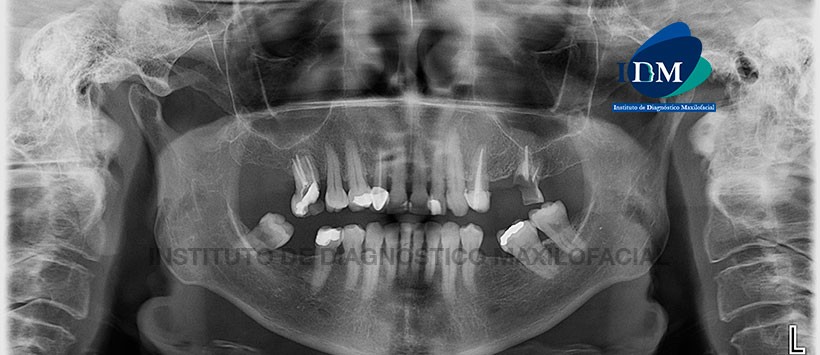

A la evaluación de la radiografía panorámica (Figura 1) se aprecia una imagen radiolúcida proyectada a nivel del piso del seno maxilar izquierdo y a nivel periapical de pieza 2.5, la misma que presenta tratamiento de conducto. La lesión presenta límites definidos y bordes parcialmente corticalizados, además se aprecia facetamiento de los contornos condilares, múltiples restauraciones y piezas con tratamientos de conductos.